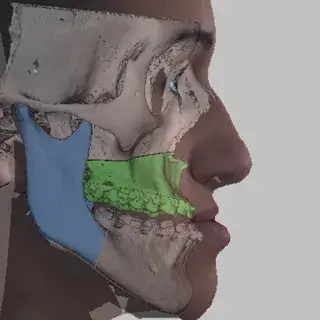

3D Systems' VSP® surgical planning solutions for craniomaxillofacial (CMF) applications received FDA clearance as a service-based approach to personalized surgery over 10 years ago.

3D Systems and Stryker Corporation have partnered to provide surgeons with best-in-class products and services for craniomaxillofacial surgeries. As a leader in personalized healthcare solutions, 3D Systems has planned and delivered devices for more than 140,000 patient-specific cases. The Stryker Craniomaxillofacial business specializes in providing patient-specific options and innovative solutions that help drive efficiencies in surgical suites. The combination of Stryker’s specialized team and advanced implants with 3D Systems' cutting-edge 3D printing technologies and expert consulting services positions both companies to provide a superior level of service to healthcare professionals who use these revolutionary solutions.